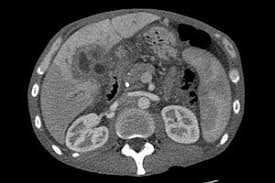

Liver Cancer And Tumors In Dogs Free Brochure On Treatment Options from www.dog-health-guide.org After examining your dog and taking a full medical history, your vet can conduct blood tests to check the levels of liver enzymes, albumin, blood urea nitrogen (bun), bilirubin, cholesterol, glucose, and a range of other substances. Some dogs will have a short span of happy days after their cancer diagnosis. According to emergency vet usa, liver failure can sometimes develop slowly and sometimes progress faster. At this point in the disease, the dog's liver can not function properly, and the dog is in a very severe condition. The incidence of cancer spreading to other parts of the body is 5%. A dog with liver failure or liver cancer can expect to live for about half a year or six months. From a medical perspective, having a dog live the average lifespan is a good result. Once a dog has reached this stage, the primary concern is making them as comfortable as possible.

Though it may take some time for the symptoms of liver disease to become apparent, diagnosis is usually a fairly straightforward process. Despite what research studies suggest, neither dog lived to their expected survival. The average survival time for dogs with one large tumor (hepatocellular carcinoma) is 3.8 years. Dogs that have had massive liver tumors removed have a good prognosis, and may live for years past the operation. This can vary substantially based on the above information. Some malignant tumors cannot be removed. In the early stages of liver failure, we see abnormal inflammation. After examining your dog and taking a full medical history, your vet can conduct blood tests to check the levels of liver enzymes, albumin, blood urea nitrogen (bun), bilirubin, cholesterol, glucose, and a range of other substances. It also depends on the type of liver cancer your pooch has. Close monitoring by your veterinarian can keep your dog as healthy as possible for as long as possible. Symptoms of stage 4 liver cancer in dogs. A dog with liver failure or liver cancer can expect to live for about half a year or six months. The impact of the liver cancer stage 4 is very bad, and the condition gets worse with time.

Homemade Dog Food For Liver Disease Recipe Easy To Make Youtube from i.ytimg.com My friend did not intend to give us a guilt trip, and neither did our vet when she laid out the same options. Therefore, it is essential not to ignore any signs of liver failure in your dog, as this may affect the need for dog euthanize. Close monitoring by your veterinarian can keep your dog as healthy as possible for as long as possible. Urine is orange in color. It also depends on the type of liver cancer your pooch has. While some pet parents discover a dog's cancer during a drastic decline in their health, others may discover the issue during a routine exam of their happy pup. The average survival time for dogs with one large tumor (hepatocellular carcinoma) is 3.8 years. If the tumor originated in the liver (primary) and if caught early, a dog can live for years after surgery.

Liver cancer in dogs is considered the most aggressive form of cancer. Life expectancy for a dog with hepatocellular carcinoma can be several months to as long as three years, depending on how localized the tumor was when discovered. Even with a surgery that is only partially successful, life expectancy goes up to a year or more. A dog with liver disease has a life expectancy of a few months to years left to live. Jaundice (gums, tongue and skin have a yellow tinge) the belly becomes hard and swollen. If your dog is 8, and the average lifespan for his weight and breed is 10 years, and your veterinarian tells you that his survival time for his cancer is about 18 months to two years, and calls that a long time, he's right from a medical perspective. Patients that receive no surgery are 15 times more likely to die of their tumor than dogs that have surgery. How long can a dog live after being diagnosed with this kind of cancer? How long can dogs live with liver cancer? However, if the complexity of liver is less then, people may survive for even couple of years. Dogs that have had massive liver tumors removed have a good prognosis, and may live for years past the operation. How long a dog can survive with cancer depends on the disease's stage (how far advanced it is), its grade (how aggressive the cancer is) and how soon the veterinarian is able to intervene in the disease process, says dr. According to scientists, the average lifespan of those dogs is about 2 to 3 months.